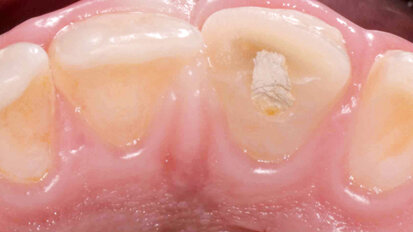

Hybridní terapie alignery